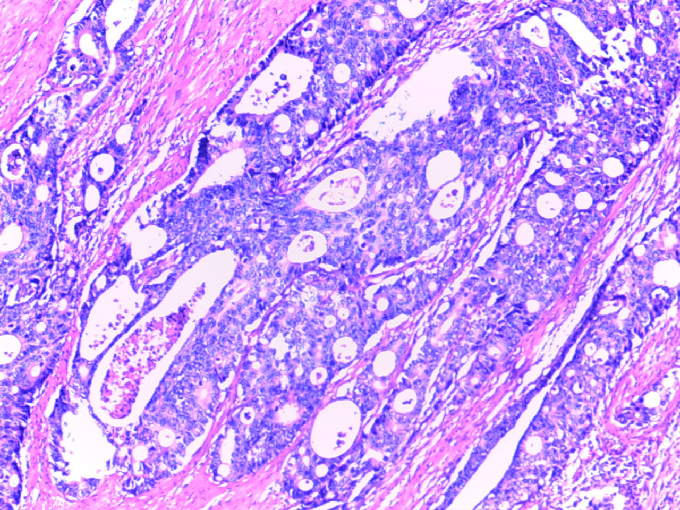

2020-02-13 术后病理

(降结肠切除标本):腺癌,中分化,溃疡型,癌组织浸润至浆膜层,见脉管内癌栓,神经见癌组织侵犯,标本上、下切缘未见癌组织残留。隆起:管状腺瘤伴低度上皮内瘤变。肠系膜查见淋巴结6枚未见癌组织转移,癌结节6枚。另见肠管壁:肠粘膜慢性炎伴局灶浅表溃疡形成,粘膜下层血管扩张、充血。

[IHC:2020069]PCK(+);Ki-67约30%+;P53(-);CDX-2(+);EGFR(±);VEGF(-);MLH1(+);MSH2(弱+);MSH6(+);PMS2(弱+)。